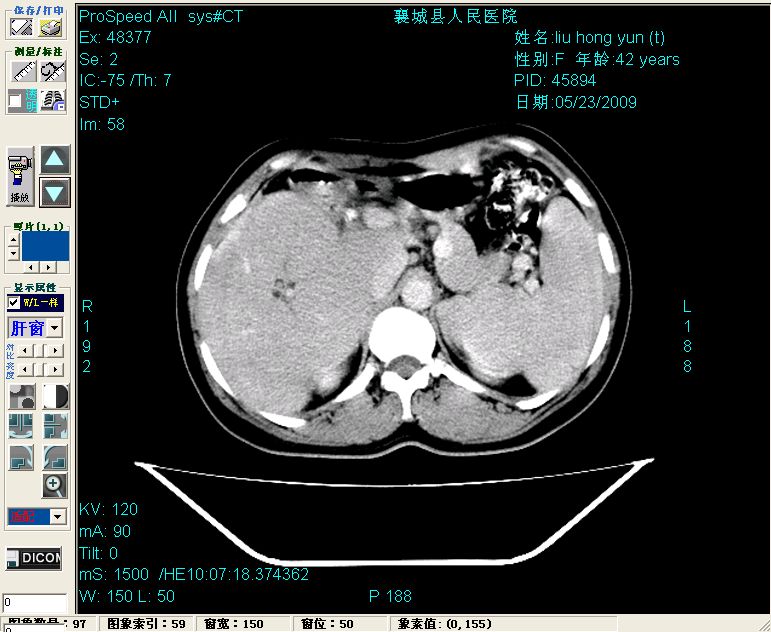

平扫:

平扫左肝外叶体积显著减小,左肝外叶见多房囊性低密度区,左肝实质及右肝前叶浅表实质呈低密度改变,左肝及右肝前叶胆管扩张,脾大